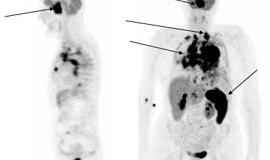

Pasaulinė limfomos žinomumo diena - ir Lietuvoje

2009-09-14 12:00